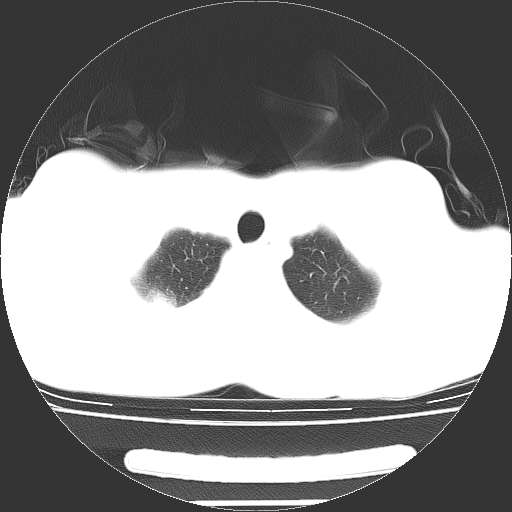

以下是引用dyqct在2008-4-29 8:43:00的发言:[br][br] 支持右侧胸腔包裹性积血。闭式引流管是不是插的太深了?

以下是引用zjzjr在2008-4-29 14:11:00的发言:[br]支持右侧胸腔包裹性积血。闭式引流管是不是插的太深了?胸腔引流,引流管快进入纵隔了.